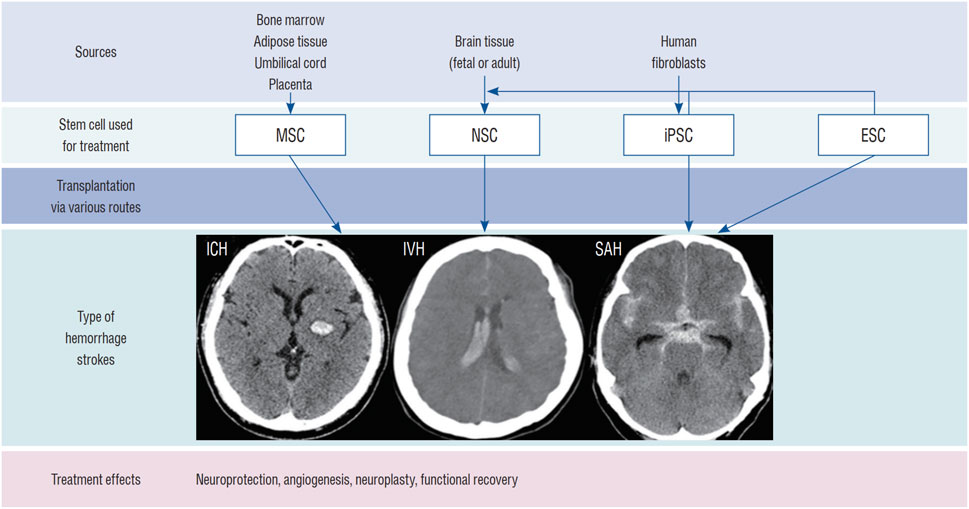

綜述結(jié)果表明,神經(jīng)干細(xì)胞治療ICH的機(jī)制涵蓋替代神經(jīng)元、免疫調(diào)節(jié)與促進(jìn)血管生成等多重途徑;其來源可分為內(nèi)源性激活與外源性移植,后者包括原代培養(yǎng)、多能干細(xì)胞分化及體細(xì)胞重編程;輸送途徑主要有立體定向腦內(nèi)注射、經(jīng)腦脊液移植及血管內(nèi)注射,各有優(yōu)劣。

其次,多能干細(xì)胞分化是另一重要外源性途徑,主要包括胚胎干細(xì)胞和誘導(dǎo)多能干細(xì)胞。胚胎干細(xì)胞雖能分化為神經(jīng)干細(xì)胞,但存在倫理爭(zhēng)議、免疫排斥和致瘤風(fēng)險(xiǎn);而誘導(dǎo)多能干細(xì)胞通過體細(xì)胞重編程獲得,避免了倫理問題,但制備過程耗時(shí)且存在類似的安全隱患,制約了其臨床轉(zhuǎn)化。

最后,體細(xì)胞重編程和轉(zhuǎn)分化技術(shù)提供了更直接的生成方式,例如利用病毒載體或轉(zhuǎn)錄因子將成纖維細(xì)胞等體細(xì)胞轉(zhuǎn)化為神經(jīng)干細(xì)胞或神經(jīng)元。盡管轉(zhuǎn)分化方法相對(duì)簡(jiǎn)便,但病毒載體可能帶來致瘤風(fēng)險(xiǎn),且轉(zhuǎn)化過程可能產(chǎn)生不必要的副產(chǎn)物,仍需進(jìn)一步優(yōu)化以提高安全性與效率。

目前,神經(jīng)干細(xì)胞移植主要通過腦內(nèi)移植、鞘內(nèi)/腦室內(nèi)注射(經(jīng)腦脊液途徑)、血管內(nèi)注射和鼻內(nèi)給藥等途徑進(jìn)行。最常用的方法是直接腦內(nèi)移植。然而,每種方法都有其獨(dú)特的優(yōu)缺點(diǎn),目前尚未確定統(tǒng)一的移植途徑(圖1)。

包括鼻內(nèi)給藥,該方法利用嗅神經(jīng)通路,可無創(chuàng)地將細(xì)胞遞送至腦內(nèi),最大限度地減少繼發(fā)性損傷。例如,Sun等人在動(dòng)物模型中發(fā)現(xiàn),鼻內(nèi)給予缺氧預(yù)處理的間充質(zhì)干細(xì)胞后,能在腦出血腦組織中檢測(cè)到這些細(xì)胞。此外,腹腔注射以及結(jié)合生物材料或納米技術(shù)的聯(lián)合給藥途徑,也在探索中,旨在進(jìn)一步提高移植細(xì)胞的存活、滯留和靶向效率(圖1)。